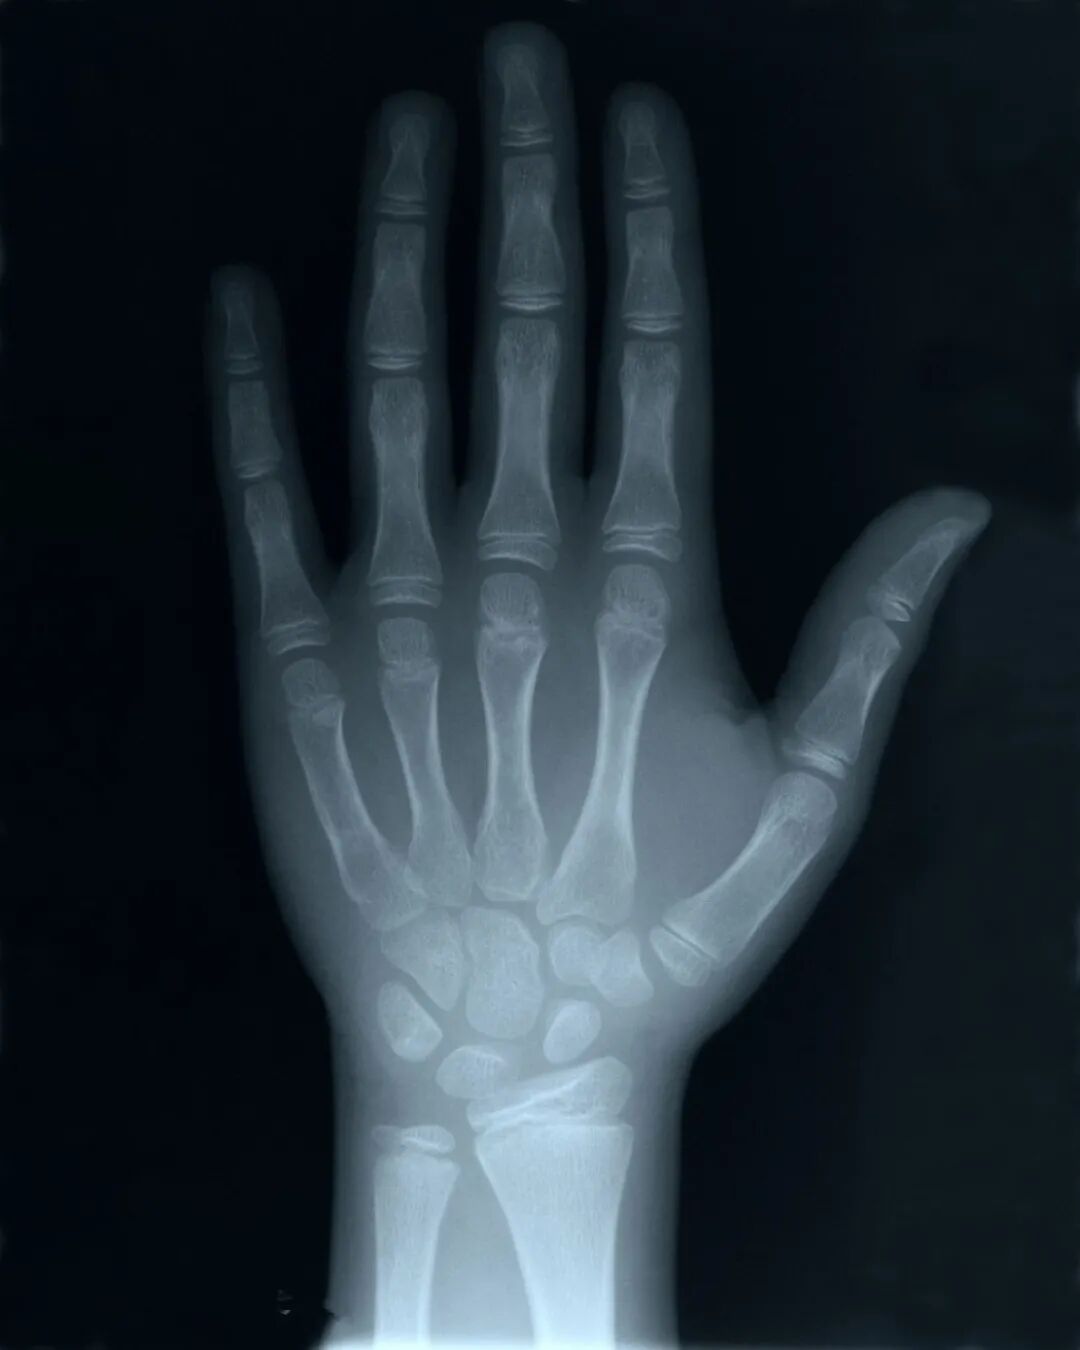

伦琴是个低调的人,但1896年1月23日,他在自己的研究所举行了他一生唯一一次报告会,公布了自己的发现。报告会上,伦琴请求维尔茨堡大学著名解剖学家克里克尔,伸出自己的手让他当场用X射线拍摄,克里克尔欣然同意。当拍好的干板经过显影,出现一位八十岁老人优美的手骨时,全场掌声雷动,爆发出欢呼。